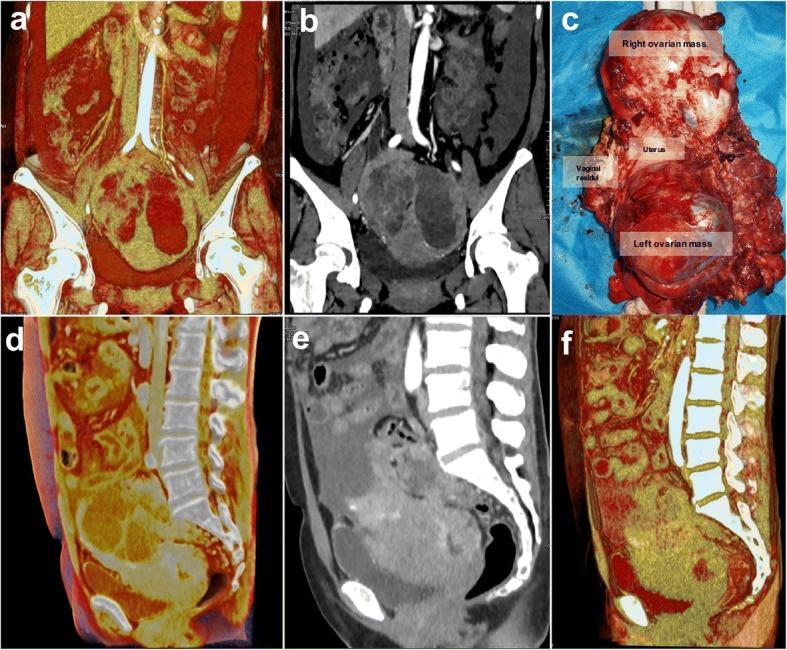

(Case 1) A 44-year-old married woman was diagnosed with recurrent ovarian cancer. CT images indicated the recurrent nodules and masses in the pelvic cavity and the upper middle abdominal peritoneum. The CR image showed that the multiple metastatic lesions and lymph nodes could not be completely removed by reoperation. The patient agreed to receive continued chemotherapy. (Case 2) A 51-year-old woman was admitted to our hospital due to abdominal distension and defecation that had increased for 6 months, with aggravation over the past 3 days. CT examination found cystic and solid masses in the bilateral ovarian area. The CR image demonstrated that the ovarian mass violated the posterior wall of the bladder and the anterior rectal wall. The preoperational imaging evaluation ensured the safety of the operation.

(病例 1)一名 44 岁已婚女性被诊断为复发性卵巢癌。CT 图像显示盆腔和中上腹部腹膜有复发性结节和肿块。CR 图像显示,多个转移病灶和淋巴结不能通过再次手术完全切除。患者同意接受继续化疗。(病例 2)一名 51 岁女性因腹胀和排便增加 6 个月,近 3 天加重而入院。CT 检查发现双侧卵巢区囊性和实性肿块。CR 图像显示卵巢肿块侵犯了膀胱后壁和直肠前壁。术前影像学评估确保了手术的安全性。